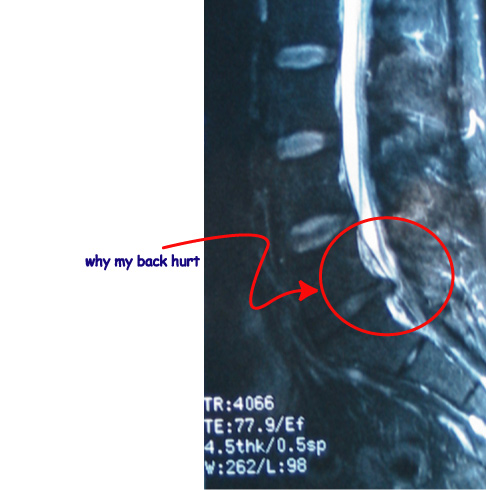

Back woes…

L4-L5 surgery, 2003